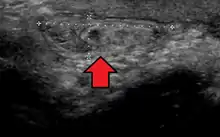

In the diagnosis of abdominal hernias, imaging is the principal means of detecting internal diaphragmatic and other nonpalpable or unsuspected hernias. Multidetector CT (MDCT) can show with precision the anatomic site of the hernia sac, the contents of the sac, and any complications. MDCT also offers clear detail of the abdominal wall allowing wall hernias to be identified accurately.[13]